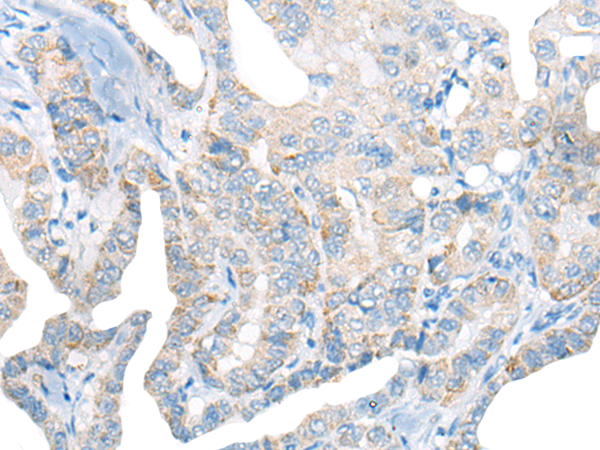

IHC positive control: |

Human thyroid cancer; |

IHC Recommend dilution: |

20-100 |